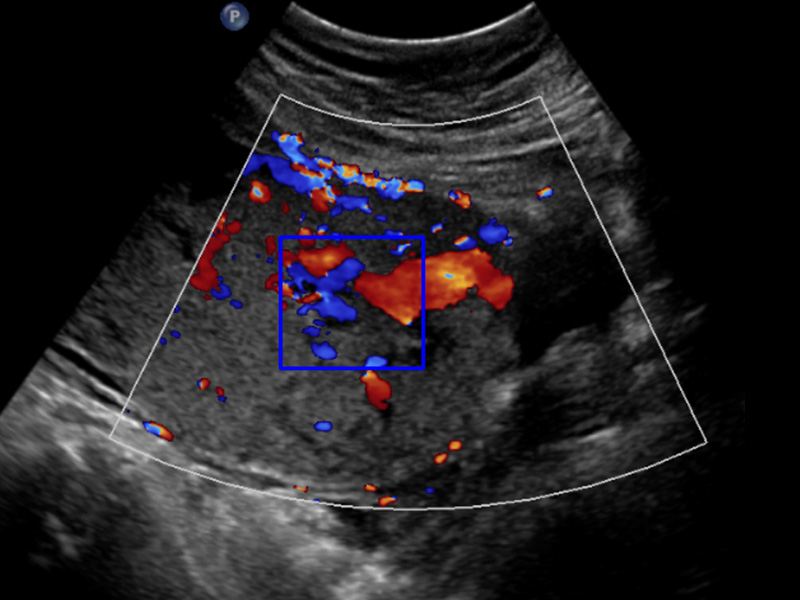

Invasive Placenta Identifcation and Classification

Invasive Placenta Identification and Classification

We are developing machine learning algorithms for detecting and classifying placenta accreta spectrum (PAS) disorder, where the placenta invades the myometrium. This will allow for earlier and more accurate diagnosis, facilitating clinical management and decreasing mortality.